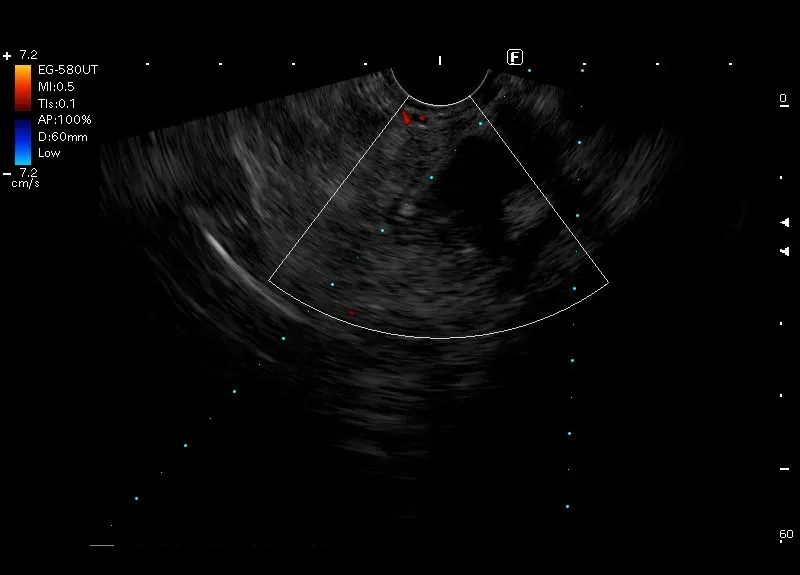

Biopsja zmiany położonej w dystalnym trzonie trzustki. Zmiana o niejednorodnie obniżonej echogeniczności i wymiarach 32x26 mm, dyskretnym przepływem obwodowym w opcji doppler i  kodującej się na niebisko „twardej” w elastografii.

Biopsja wykonana igłą 22G (FNB) z pobraniem materiału do badania histopatologicznego.